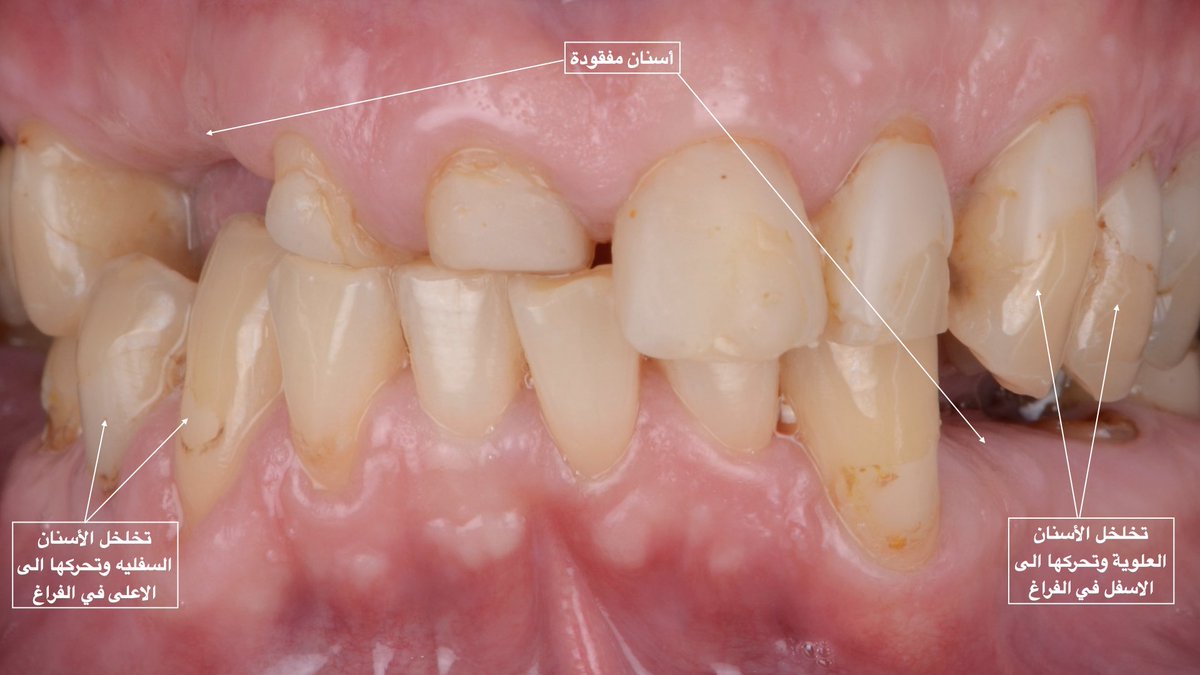

Preservation > Generation

الشيء الثاني وهو جداً مهم، الفراغ الحاصل بعد فقدان أي سن يؤدي لتحرك (خلخلة) الأسنان المحيطه بالفراغ من مكانها مؤثرا بذلك على تطابق الاسنان مع بعضها البعض. وايضا يؤدي لإنحسار في فراغ السن المفقود فيصبح غير كافي للتعويض (التركيب) مستقبلا،،، يتبع

و قد يحتاج المراجع الى عمل تقويم لتعديل مكان الاسنان. يمكن تفادي ذلك لو كانت الخطة العلاجية صحيحة منذ البداية بعمل تركيبة مؤقتة لتحافظ على المسافة الطبيعية الى أن يحين وقت زراعة الاسنان او تعويض الاسنان بالتركيبة الثابتة (الجسر).